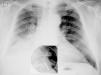

Paciente masculino de 66 años, con diagnóstico de adenocarcinoma de pulmón (estadio iv, con metástasis óseas, en tratamiento con quimioterapia), que desarrolla tromboembolismo pulmonar (TEP), por lo que se indica anticoagulación con heparina, y posterior administración de dicumarínicos. A los 2 meses presenta nuevo episodio de TEP bajo adecuado rango de anticoagulación, por lo que se coloca filtro en vena cava inferior (ELLA Filter®, ELLA-CS sro, República Checa), y continua tratamiento farmacológico con enoxaparina (100mg c/12 horas) más acenocumarol. A los 40 días el paciente presenta disnea súbita y dolor torácico. Se realiza angio-tomografía de tórax, donde se evidencia migración de filtro de vena cava inferior en proyección de la arteria pulmonar izquierda, con trombo adherido, e imagen de trombo pulmonar sub-lobar derecho (fig. 1). Se decide anticoagulación con heparina sódica endovenosa. Angiografía digital evidencia migración de filtro de vena cava inferior a rama lobar inferior izquierda asociado a trombo intra filtro, que se insinúa a bronquio fuente derecho, con fragmento en ramo lobar derecho. Se intenta retirar el filtro, pero es imposible, dado que el mecanismo de cierre y retracción del mismo se encuentra en una rama pulmonar secundaria, en posición distal. El paciente es dado de alta con doble anticoagulación (enoxaparina más acenocumarol). Una radiografía de tórax efectuada a los 2 meses, demuestra la permanencia del filtro en campo pulmonar izquierdo (fig. 2). A 6 meses de seguimiento el paciente permanece vivo, continuando tratamiento quimioterápico, y con hipertensión pulmonar crónica, con presión sistólica pulmonar de 58mm Hg (evaluada por ecocardiograma).